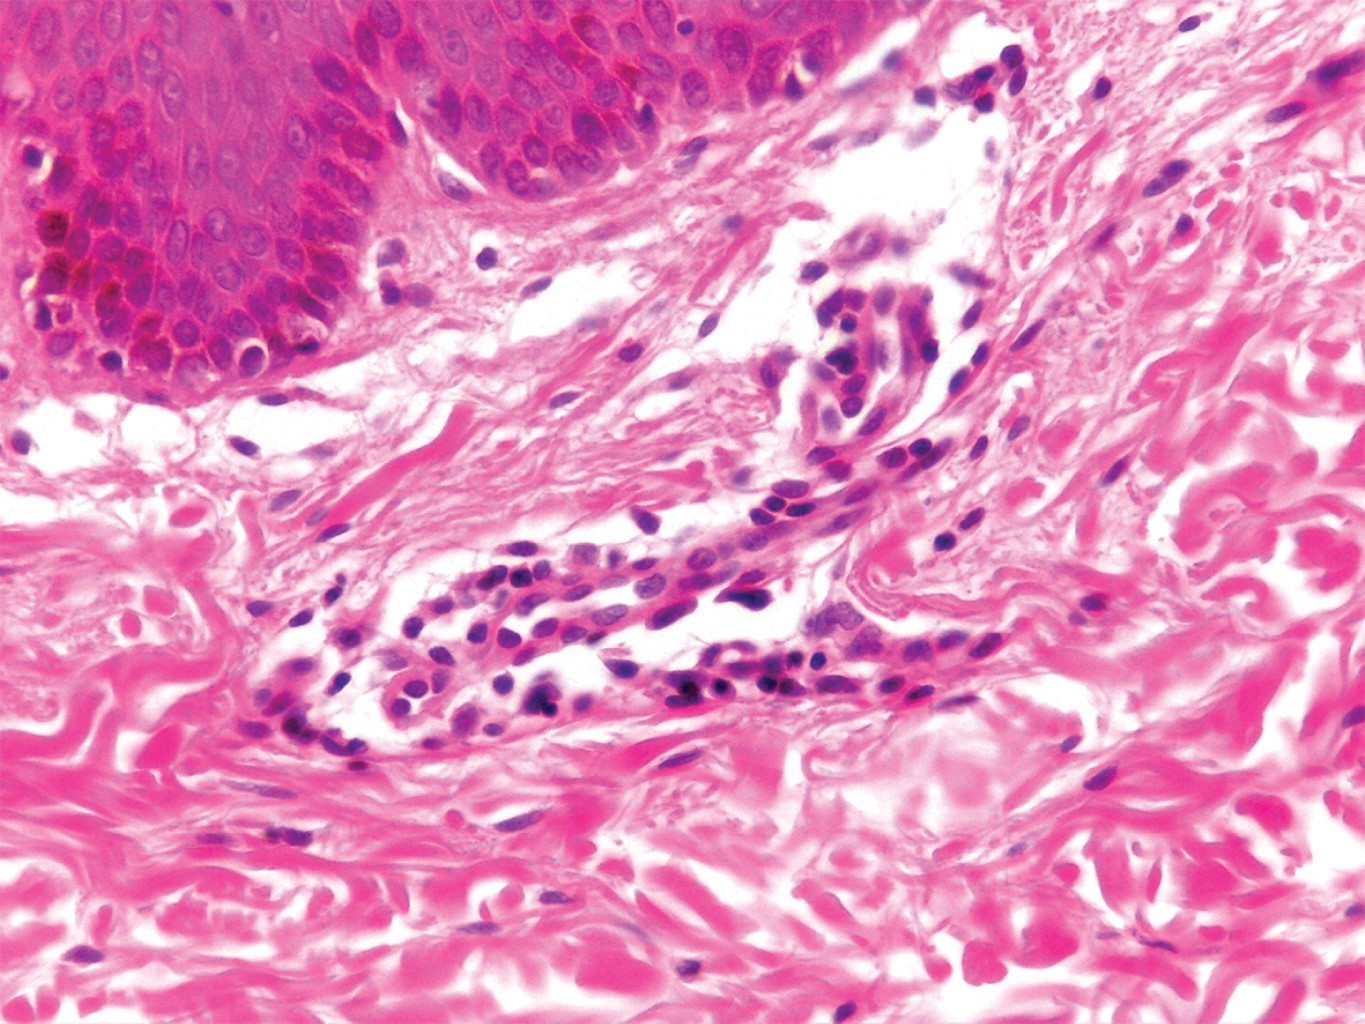

En la variedad superficial pueden observarse cambios epidérmicos de paraqueratosis con espongiosis, con infiltrado denso de linfocitos e histiocitos (y con menor frecuencia, de eosinófilos) alrededor del plexo vascular superficial (Figuras 4 y 5). El edema en la dermis papilar es mínimo. En la variante profunda, el infiltrado invade hasta el plexo vascular profundo. Tiene una disposición característica en "manguito" alrededor de vasos superficiales y profundos; las células pueden extenderse hacia las paredes de los vasos pequeños; sin embargo, nunca se observa extravasación de fibrina; es una pseudovasculitis. La epidermis es prácticamente normal, aunque se han descrito queratinocitos apoptóticos y, ocasionalmente, cambios vacuolares.3 Weyers y colaboradores estudiaron 73 casos con EAC, 50 de ellos con la variedad superficial, y 32 con la profunda. En aquellos superficiales, se observó en 100% infiltrado superficial, 80% presentó espongiosis (que generalmente era focal), así como paraqueratosis en dos tercios de los pacientes. La histopatología de los 32 casos de EAC profundo demostró la presencia de infiltrado profundo, y mínima o ausente paraqueratosis; en 69% de los casos se apreciaron melanófagos.3

Figura 4

Figura 5